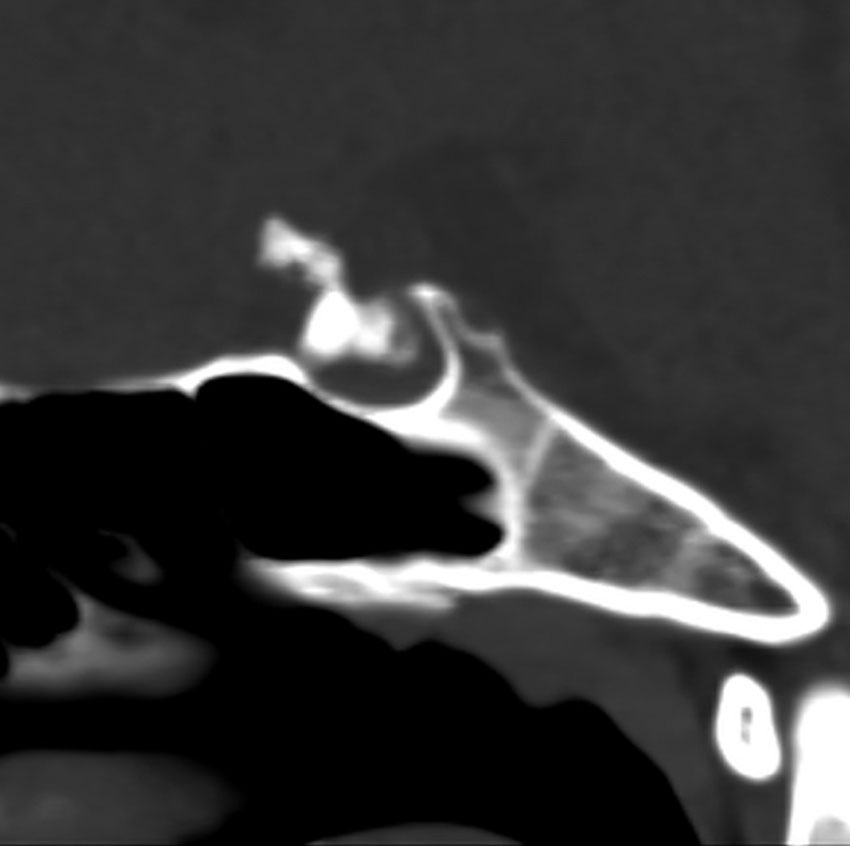

鞍隔膜下 infradiaphragmic type

7歳の子が視力障害で発症しました。両耳側半盲という症状です。典型的な鞍隔膜下頭蓋咽頭腫です。ガドリニウム造影剤を入れないMRIでみえる,黄色い矢印の先の白い高信号は抗利尿ホルモンです。ですから下垂体機能もまだ残っていて,尿崩症はありません。視力障害が戻らないことがあるのでなるべく早く,経鼻的な手術で摘出した方がいいものです,簡単 o(^-^)o